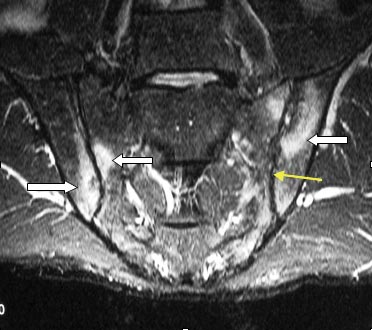

(1)X线平片:关节囊肿胀;关节间隙增宽,随后则关节间隙狭窄,承重面骨质破坏; 半脱位;骨性关节强直;(2)CT:肿胀、积液、骨端破坏;(3)MRI:滑膜炎、积液、软骨破坏、软组织受累范围

临床表现:红、肿、热、痛;白细胞升高,承重关节(髋、膝),滑膜充血水肿,关节腔大量渗液,MR优势:显示早期关节软骨破坏、滑膜增厚、积液。

X线表现:1、急性期:关节囊肿胀、关节间隙增宽,关节囊和韧带破坏可致关节半脱位及脱位;2、病变进展迅速,关节软骨破坏,关节间隙狭窄;3、肉芽组织增生,破坏软骨下骨,承重部分出现早和明显;4、愈合期骨质增生硬化,严重时骨性强直